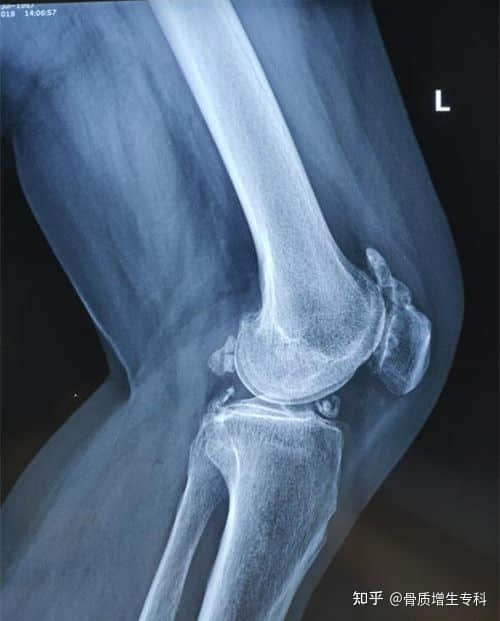

膝关节游离体,是关节内软骨、滑膜,剥脱下来的碎片,可在关节内移动,又称“关节鼠”,有的也会与组织相连。骨质增生专科:游离体不会被人体吸收,不存在自愈。

在关节活动时,游离体移动,卡在关节某处,形成卡顿,关节无法活动、疼痛;稍活动后,卡顿消失,关节又可自如活动、疼痛消失。

有的人偶尔出现关节卡顿交锁,可以不用处理;反复卡顿交锁的话,需要做个很小的手术,关节镜取出游离体。

出现游离体反复交锁,不手术取出的话,容易磨损关节面,加快形成骨质增生,造成骨关节炎、滑膜炎,形成骨性关节炎的恶性循环。